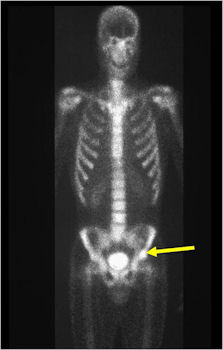

Bone Scan:

- Double Density Sign: Hot within the nidus and less intense accumulation peripherally within the sclerotic bone